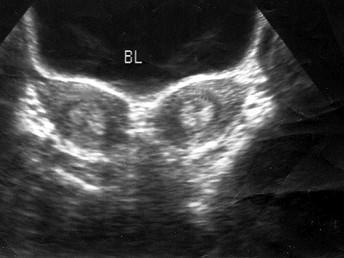

盆腔超声检查如图,最可能的诊断是?(?)A.幼稚子宫B.双子宫C.双角子宫D.畸胎瘤E.正常声像图